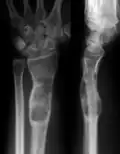

X-ray showing calcified enchondromas localized in finger a 37-year-old patient affected with Ollier disease -

Abnormal bone growth such as shortening or thickening and deformity may be observed in patients of Ollier disease. These bone lesions are visible at birth using radiography but are usually not screened or examined for until clinical manifestations present during early childhood. However, some patients may exhibit no signs of any symptoms.[1] One study found thirteen to be the mean age of diagnosis in patients with Ollier disease. In an X-ray, there would normally be the presence of several homogeneous lesions of an oval or elongated shape with bone edges that are slightly thickened.[3] With age, these lesions may calcify and appear as diffusely minute spots or stippled. Fan-like septations or streaks would be indicative of the presence of several enchondromas. Early detection and consistent and repeated monitoring is important in order to prevent and treat any potential bone neoplasms.